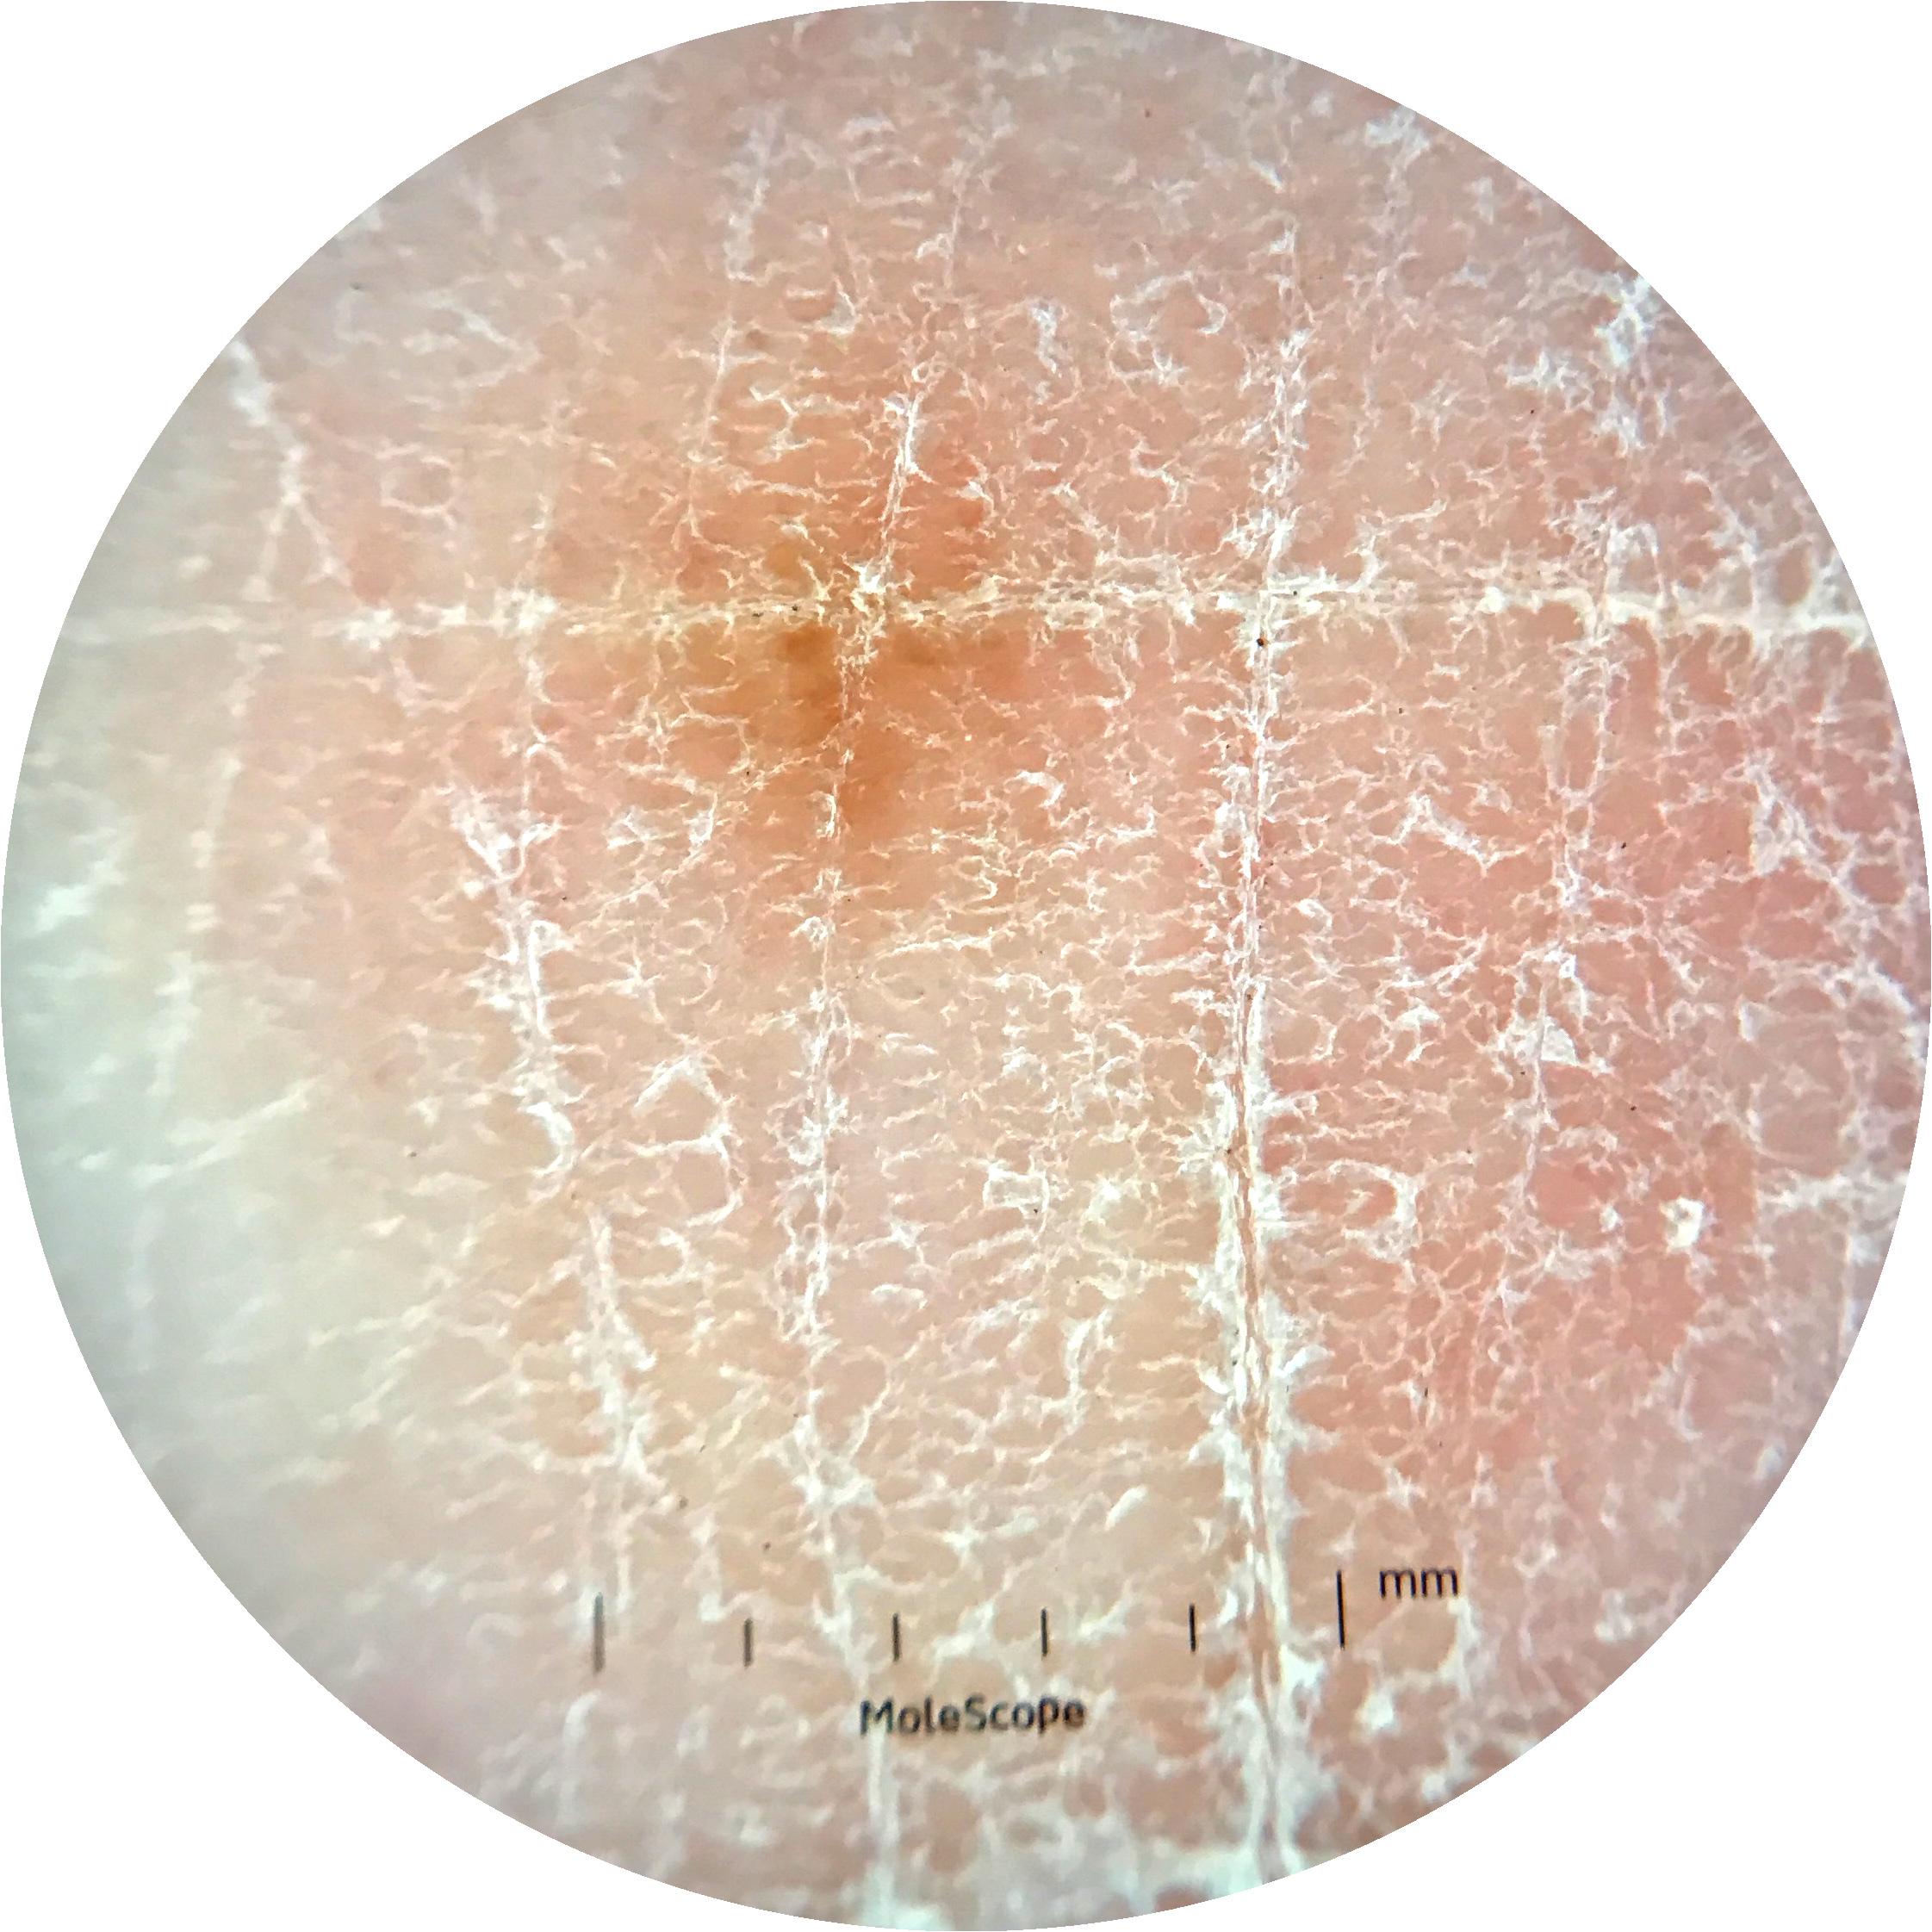

anatom_site_1 Upper extremity

anatom_site_general upper extremity

diagnosis_1 Benign

image_type dermoscopic